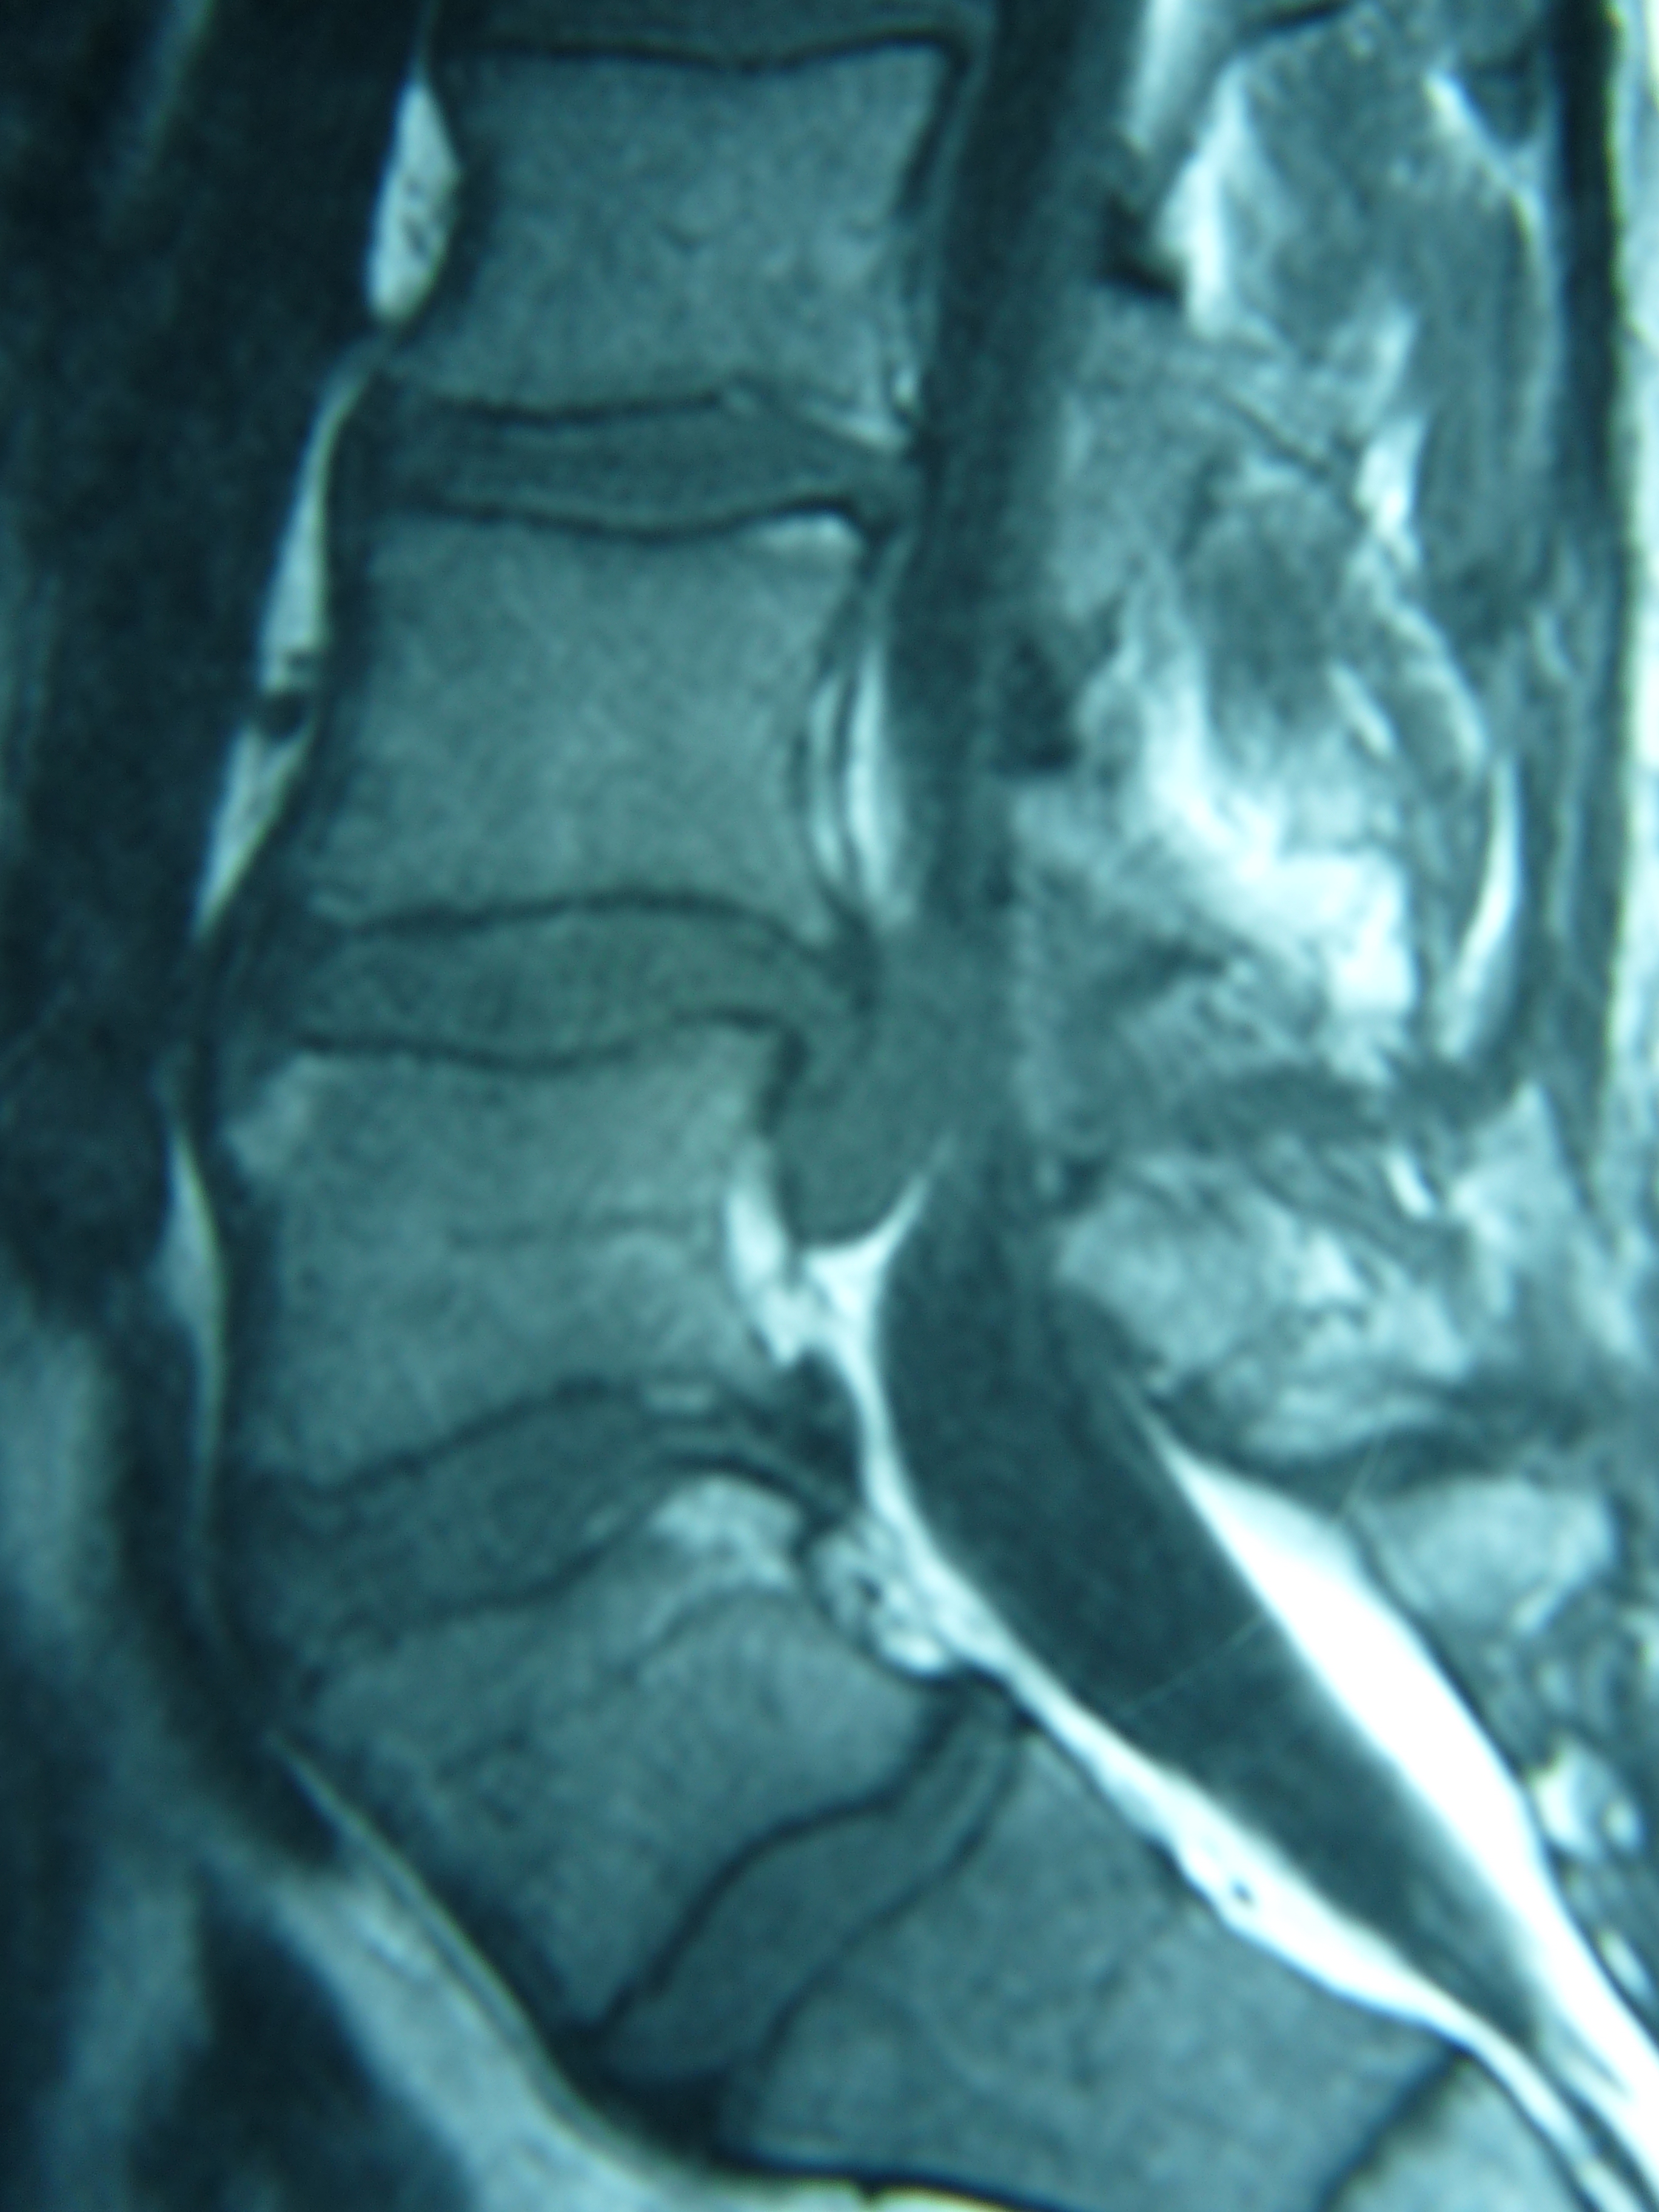

Εικόνα 2: Μαγνητική τομογραφία α,β,γ. Οβελιαία (Saggital) δ,ε. Εγκάρσια (Axial) ζ. Μετωπιαία (Coronal) , ακολουθίες Τ1-Τ2

Παρατηρείται έκθλιψη του πυρήνος του μεσοσπονδυλίου δίσκου (Επίπεδο Ο4-Ο5) προς τ’ αριστερά και όπισθεν του σώματος του 4ου οσφυικού σπονδύλου.

Αποφασίστηκε η χειρουργική αντιμετώπιση. Εγένετο αφαίρεση του εκθλιβέντος (sequestrum) τμήματος του μεσοσπονδύλιου δίσκου και συμπληρωματικά πραγματοποιήθηκε σταθεροποίηση του σπονδυλικού επιπέδου Ο4-Ο5 με δυναμικό σύστημα σπονδυλοδεσίας.

Εικόνα 3: Μετεγχειρητικές ακτινογραφίες Ο.Μ.Σ.Σ. α. Προσθιοπισθία β. Οβελιαία

Παρατηρείται το σύστημα δυναμικής σταθεροποιήσεως που επιτρέπει περιορισμένου εύρους κινητικότητα της σταθεροποιημένης περιοχής.

Η μετεγχειρητική πορεία του πάσχοντος υπήρξε εξαιρετική από πλευράς πόνου και νευρολογικής αποκαταστάσεως